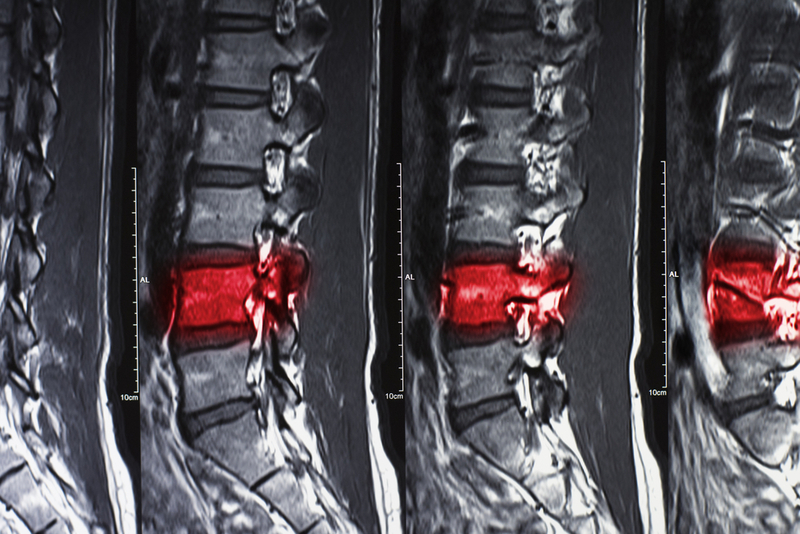

He shared the case of a 21-year old woman who had suffered a fall which led to severe pain in her back followed by retention of urine and weakness in lower limbs. "MRI revealed that she had lumbar fracture of L1 and spinal cord compression by the fractured bone. She had to undergo two surgeries to decompress and stabilize the spine," Prasad said.